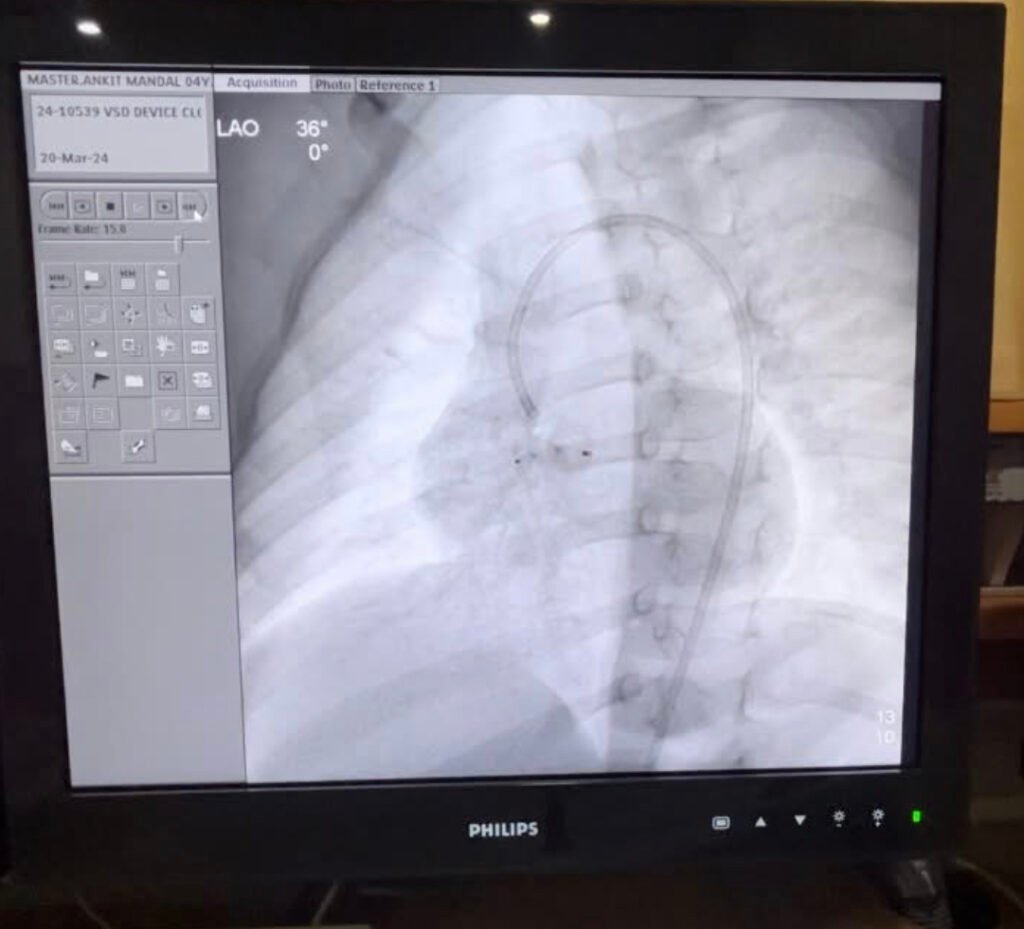

VSD Device Closure

Pioneering VSD device closure in coastal Andhra Pradesh. Successfully did a VSD device closure at Medicover hospitals, MVP colony, Visakhapatnam. Thanks to Dr Surendhra , Praveen senior cath technician, sarala sister and the entire team for the support. I thank almighty for his blessings